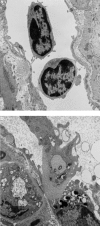

Leucocyte recruitment to sites of intestinal inflammation is a crucial, multi-step process that leads ultimately to the accumulation of cells in the inflamed tissue. We established a new in vivo model system of experimental colitis to quantify leucocyte-endothelial cell interaction and leucocyte extravasation in the inflamed mucosa of the colon. Furthermore, we investigated the pathophysiological role of ICAM-1 in the intestinal microcirculation in vivo. Using the model of dextran sodium sulphate (DSS)-induced acute and chronic colitis in mice, in vivo microscopy was performed in the colonic submucosal postcapillary venules and the submucosal collecting venules in normal or inflamed murine colonic segments. ICAM-1 expression was blocked by an anti-ICAM-1 monoclonal antibody or by suppressing NF-kappaB activation by gliotoxin. Significant increases in leucocyte adhesiveness (51-fold in postcapillary venules, 30-fold in collecting venules, P < 0.01) and extravasation (6.5-fold) could be demonstrated as early as day 2 of DSS-application in acute colitis (P < 0.01). This was paralleled by increases in both the histological damage scores and myeloperoxidase activities. In chronic dextran sodium sulphate-induced colitis significant increases in leucocyte-endothelium interactions and leucocyte extravasation were observed. Blocking ICAM-1 expression with a monoclonal antibody or gliotoxin, leucocyte sticking and extravasation were significantly down-regulated in vivo compared to controls (> 70%; P < 0.01). This new model system offers the possibility to specifically assess the role of adhesion molecules in the colonic mucosa in vivo as well as to investigate and quantify the effectiveness of experimental therapeutic approaches in acute or chronic intestinal inflammation.